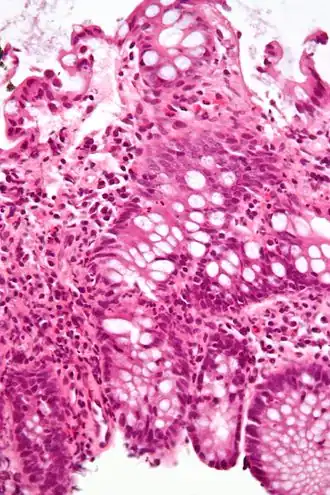

Коли́т (лат. colitis; от греч. kolon — толстая кишка и греч. itis — воспалительный процесс) — воспалительное заболевание слизистой оболочки толстой кишки. Чаще болеют мужчины 40—60 лет и женщины 20—60 лет. Протекает остро или хронически. Считают, что проявления хронического колита имеют место у каждого второго больного с проблемами органов пищеварения. К колитам предрасполагают снижение общей резистентности организма, недостаток растительной клетчатки в пище, воспалительные процессы аноректальной зоны (восходящая инфекция).

Диагноз колита основывается на типичных жалобах, сборе анамнеза (перенесенный гастроэнтероколит, пищевая токсикоинфекция и др.), физикальном обследовании (пальпация живота, пальцевое исследование, аноскопия), инструментальных методах (эндоскопия, ректороманоскопия и ирригоскопия с введением контраста — сульфата бария) и лабораторных данных. Инструментальные методы позволяют визуально контролировать состояние слизистой оболочки, и дифференцировать обычный колит от язвенного колита.